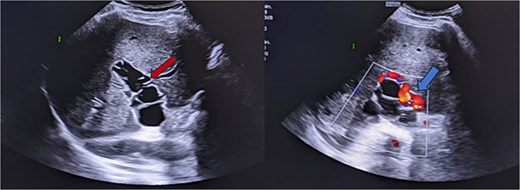

An abdominal ultrasound was performed, which showed multiple cystic lesions within the portal vein, extending to all its anterior and posterior division branches, with venous collaterals at the hepatic hilum, suggesting a portal cavernoma (Fig. 1). A computed tomography (CT) scan and magnetic resonance imaging (MRI) were subsequently conducted for further evaluation, revealing signs of previous left hepatectomy with a multivesicular cyst at the resection margin (stage IIIB) and another in segment V below the liver. The imaging confirmed the presence of multiple hepatic cysts within the portal system, sparing the superior mesenteric vein, spleno-mesenteric trunk, and biliary system (Fig. 2), along with serpiginous collateral venous channels around the hepatic hilum, the pancreatic head consistent with a portal cavernoma and a dilatation of the left gastric wall causing varices of the posterior gastric wall (Fig. 4). Indicating a very rare case of intraportal hydatidosis complicated by signs of portal hypertension (Figs 1–4). Following a thorough review at a multidisciplinary consultation meeting, the surgical option was decisively rejected. This was due to the significant risks of pulmonary embolism due to parasites and thrombotic complications in the portal system or its bypass routes. These risks were deemed too high, especially given the uncertain benefits of surgery, considering the chronic nature of the obstruction, which had been supplanted by the portal cavernoma, and the asymptomatic nature of portal hypertension. As a result, the decision was made to opt for regular monitoring with medical treatment based on albendazole and anticoagulants.

Ultrasound images reveal the presence of multiple liquid cystic formations that do not respond to colour Doppler in the lumen of the portal trunk and its dividing branches. These findings are in relation to portal hydatidosis, with the development of a portal cavernoma.